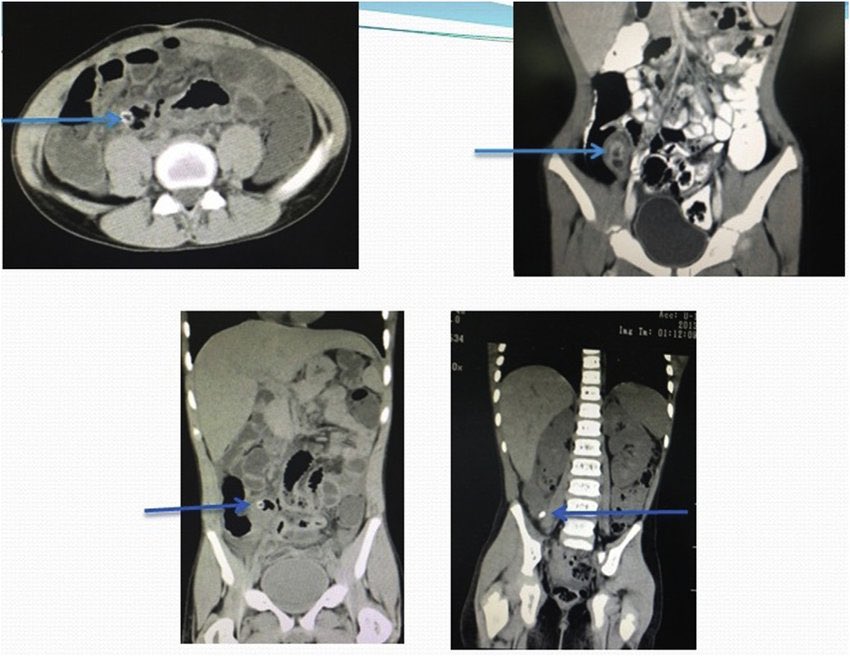

Acute pancreatitis:

NO ANTIBIOTIC UNLESS REALLY SEVERE OR EVIDENCE OF INFECTION (FNA or bubbles in CT= infected necrosis)

Step up approach always for the 4 major complications (see pix)

Always feed your pt unless vomiting or severe pancreatitis

Mortality of infected necrosis>20%